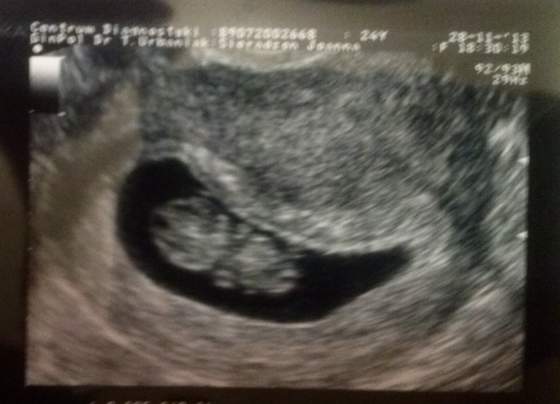

Marchew Piękne zdjęcia!!!